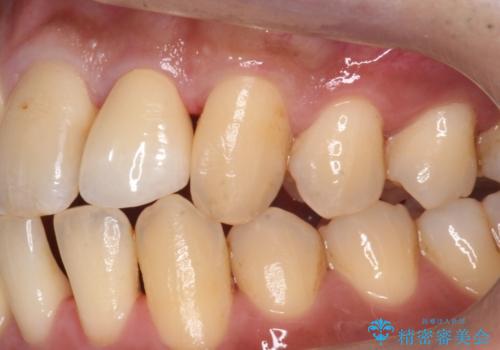

ジルコニアクラウンスペシャルはジルコニアクラウンスタンダードに比べ

色のバリエーションが多く、よりご自身の天然歯の色と合うように作れます。

自然な被せ物が入り、大変満足して頂けました。